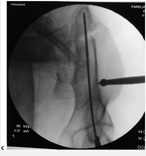

4-      crescent fracture  : اين آسيب كه همان آسيب ناشي از كمپرشن لاترال ميباشد با فيكساسيون قسمت خلفي و پيچ ايليوساكرال از طريق پوست و با كنترل فلورسكوپ درمان ميشوند و سپس در زير فلوروسكوپ عدم ثبات در قدام حلقه لگني ارزيابي شده و در صورت وجود عدم ثبات   (instability)  اقدام به فيكساسيون قسمت قدام لگن نيز خواهد شد.

راديوگرافي AP  6 ماه پس از عمل جراحي   (A)  Intel view  (B  ) و out let view  (C  )CT  اسكن مربوطه نشاندهنده شكستگي ايلياك و دررفتگي ساكروايلياك كه در وضعيت آناتوميك فيكس شده و جوش خورده است

5-      شكستگيهاي ساكروم: درمان انتخابي ريداكشن شكستگي زير كنترل فلوروسكوپ و كارگذاري پيچ ايليوساكرال براي فيكساسيون است كه مستلزم وجود چند كمك براي جراح- كشش مداوم حين عمل جراحي و كنترل روي ايليوم براي جااندازي ميباشد و مجموعاً عمل جراحي مشكلي است. برخلاف ساير جاها در لگن كه ابتدا فيكساسيون قسمت خلفي انجام ميشود و در صورت لزوم قسمت قدامي لگن،در شكستگيهاي ساكروم كه حلقه لگن در قسمت قدامي هم آسيب ديده باشد ابتدا آسيب قدامي فيكس ميشود و بعد اقدام  به فيكساسيون شكستگي ساكروم خواهد شد

شكستگي بال ايلياك و شكستگي ساكروم و شكستگي راموس فوقاني پوبيس كه توسط پيچ ايليوساكرال و تحت كنترل فلوروسكوپ، تثبيت ميشود.